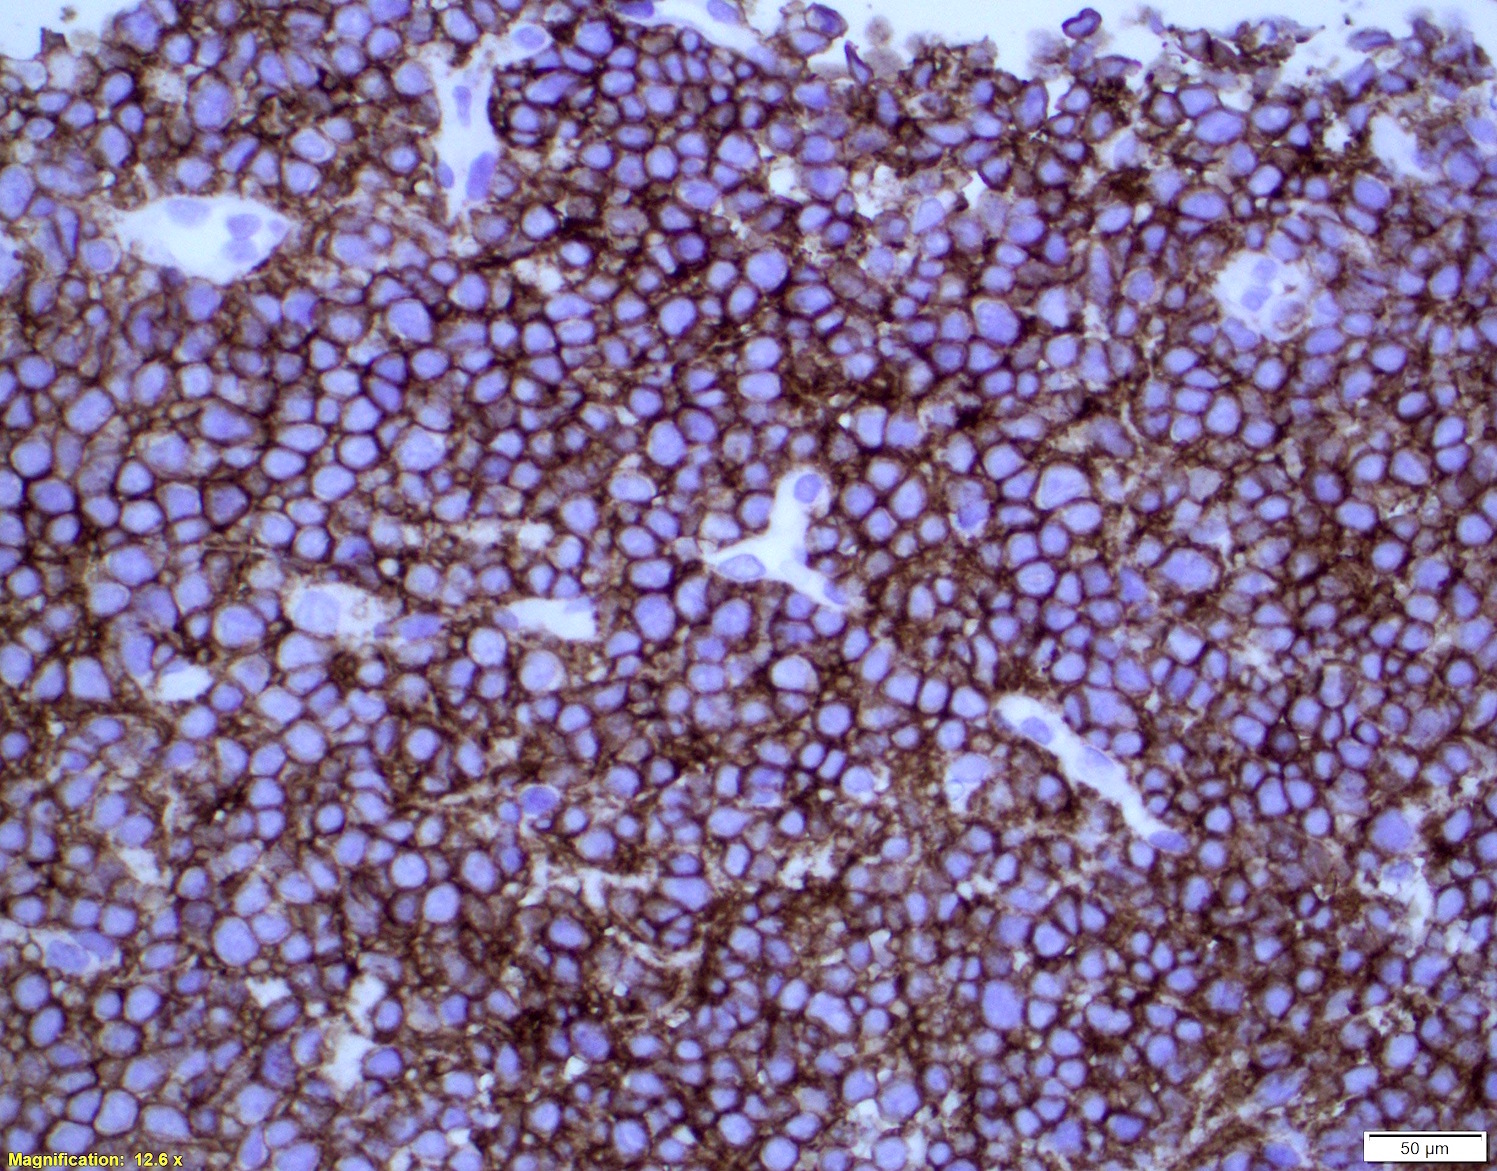

- Immunophenotype similar to classic mantle cell lymphoma

- Cyclin D1

- CD19, CD20, CD43, sIg, IgM with or without IgD

- CD5 (> 95%), SOX11 (> 90%)

- Note: Ki67 index is not sufficient to classify as blastoid or pleomorphic subtype